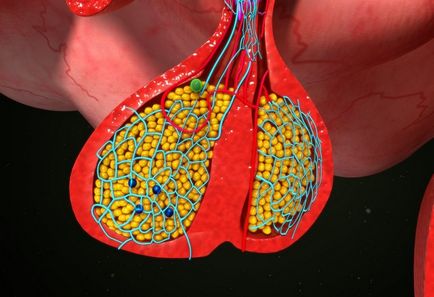

hormon de crestere (somatotropina, hormonul de creștere, hormonul de creștere) produs de adenohipofiză. În cazul în care sângele conținute într-o cantitate suficientă, astfel încât nu au nici diferite patologii asociate cu creșterea la copii, adolescenți (gigantism, nanism). nu are nici un impact asupra embrionului este nu, copilul se naște cu o creștere normală (chiar dacă el are deficit ereditar de hormon de creștere). Pentru adulți acest hormon este de asemenea esențială, deoarece îndeplinește alte funcții importante.

Este necesară pentru stimularea secreției de insulină. Împreună, acești hormoni crește preluarea tisulară a glucozei. hormon de creștere insulin-like a prelungit efect.

Violarea sinteza hormonului de creștere afectează în mod negativ metabolismul glucidelor. Când gigantism, acromegalie (când hormonul de creștere este produs într-o cantitate în exces) apare rezistenta la insulina. Țesuturile pierde sensibilitatea la efectele insulinei, deci nu absorb glucoza.

Deoarece patologii metabolice asociate cu hormon de creștere în exces și a altor boli apar. glande endocrine perturbate, sistemul cardiovascular. Datorită faptului că hormonul de creștere inhibă producția de renină și aldosteron, dezvoltă hipertensiune arterială rezistentă. De asemenea, un exces de hormon favorizează apariția polyposis, carcinoamele intestinale.

În cele mai multe cazuri, motivul pentru nivelul ridicat al hormonului de creștere în sânge este o tumoare pituitara - somatotropinoma.

Contribuie la hipersecretie cronică de hormon de creștere ar putea chiar sarcina. Pentru că în această perioadă, uneori se dezvolta hiperplazie celule pituitare eozinofile responsabile pentru producerea hormonului de creștere, atât de acromegalie de multe ori sufera de femei. Dar, în 99% din cazuri cauza excesului de hormon de creștere în sânge este somatotropinoma. Aceasta este o tumoră benignă a glandei pituitare anterioare.